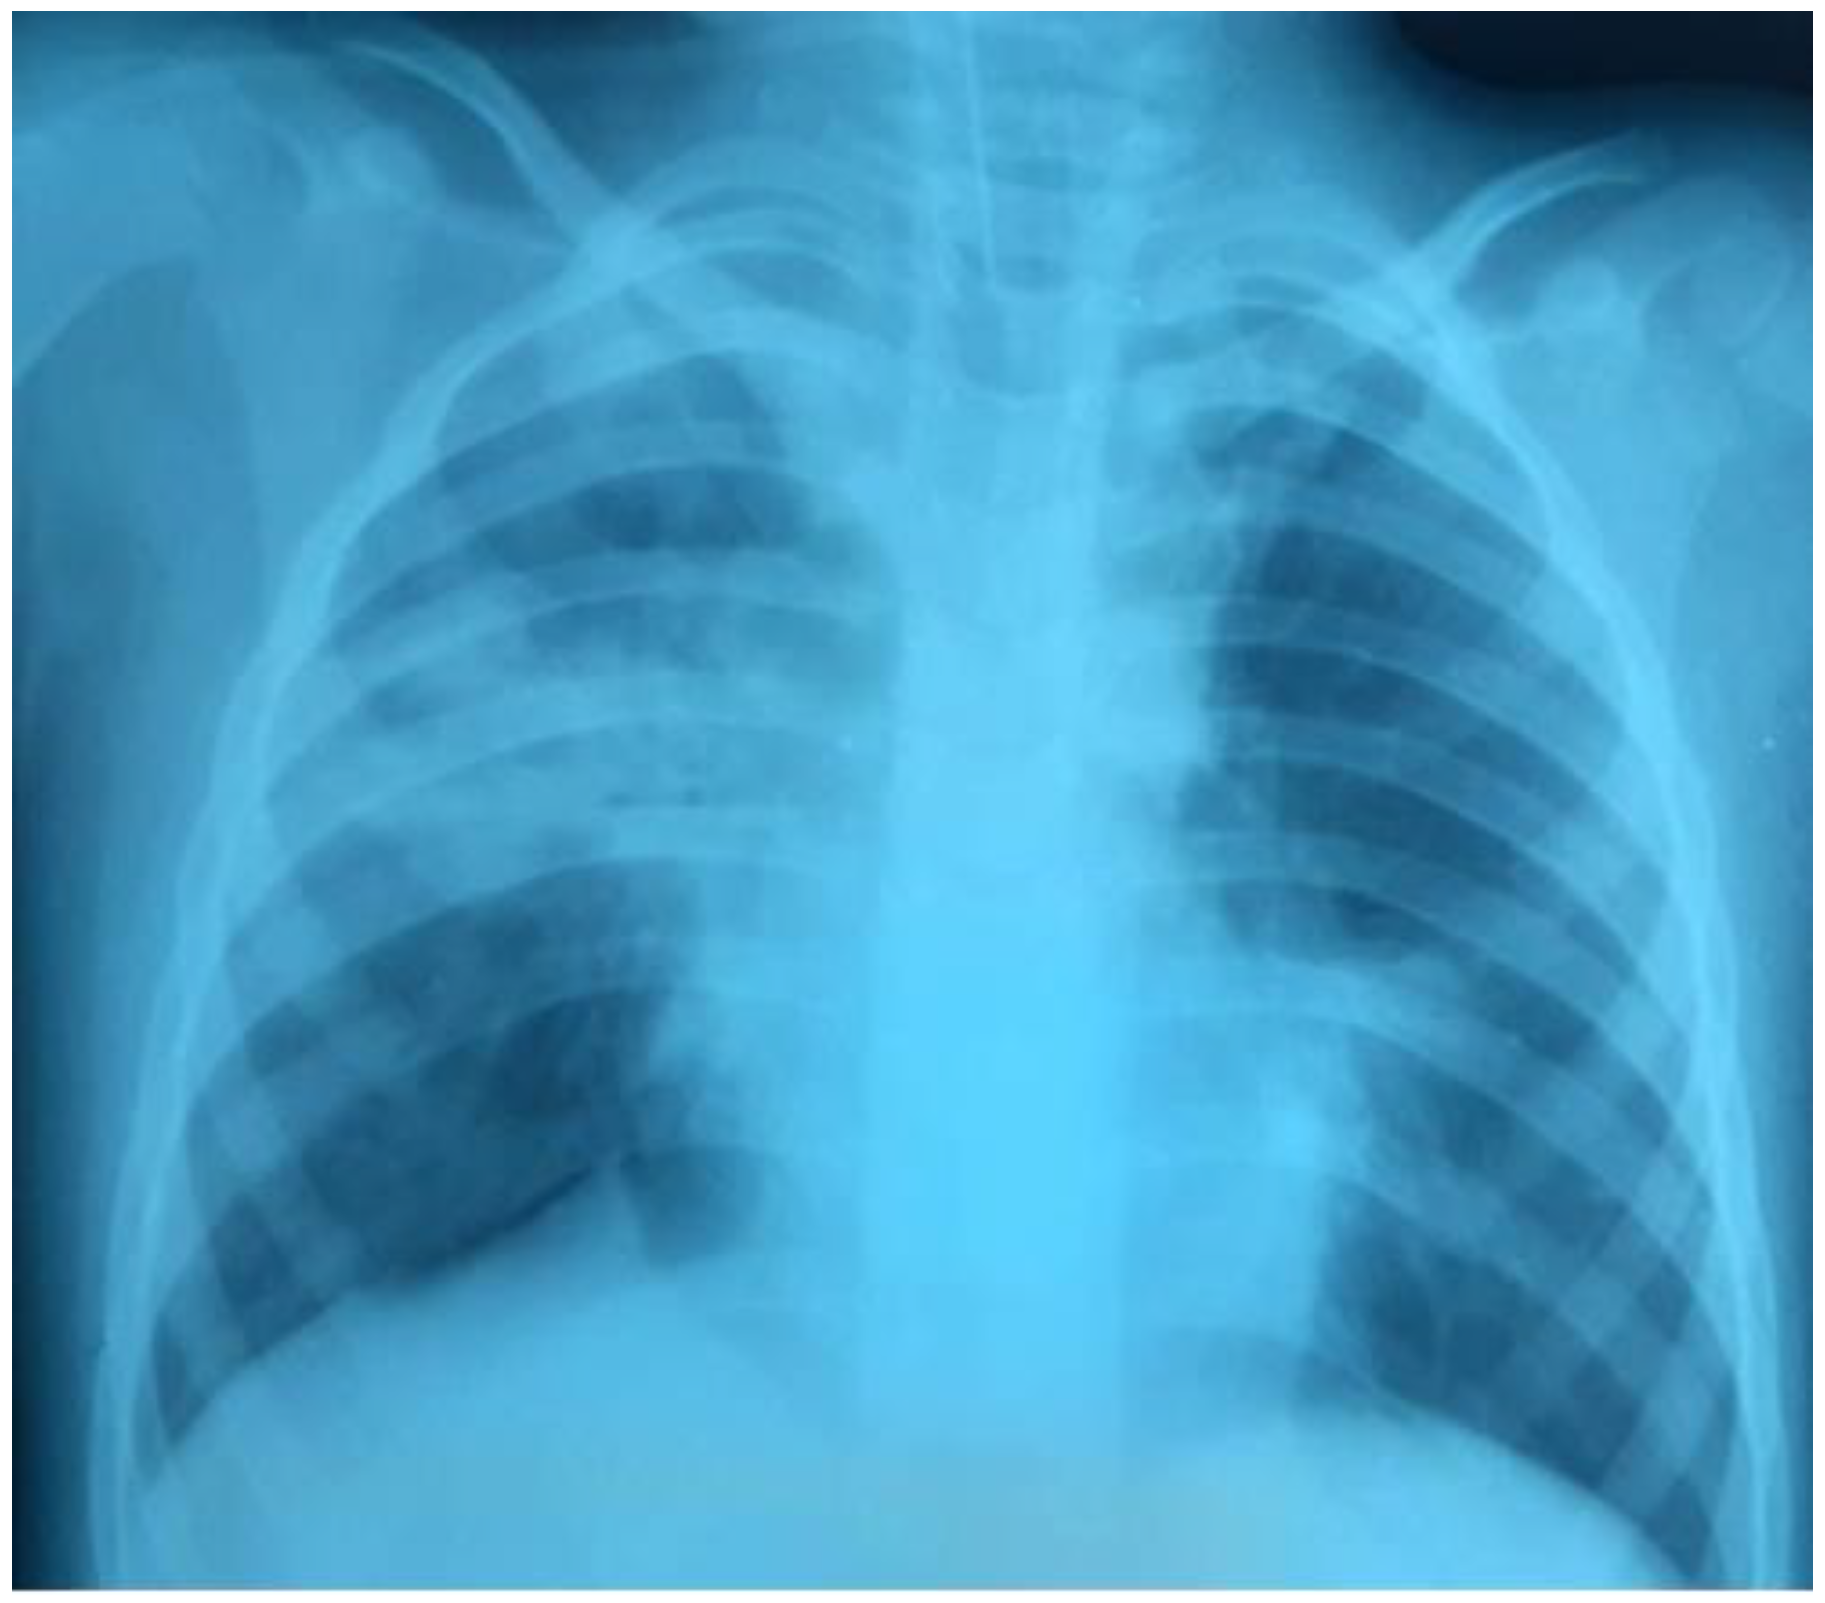

There was a further progression of RF and hypoxemia (PaO2/FiO2 117) on the background of NIV CPAP/PSV in the child, as well as the deterioration of the neurological status of the patient on the Glasgow scale (the decrease in the GCS score from 14 to 12). The control chest X-rays (performed in 24 hours) revealed a deterioration of the radiological imaging (Figure 2).

Figure 2.

The increase of the intensity of opacities on the right side, the appearance of new bilateral infiltrates.